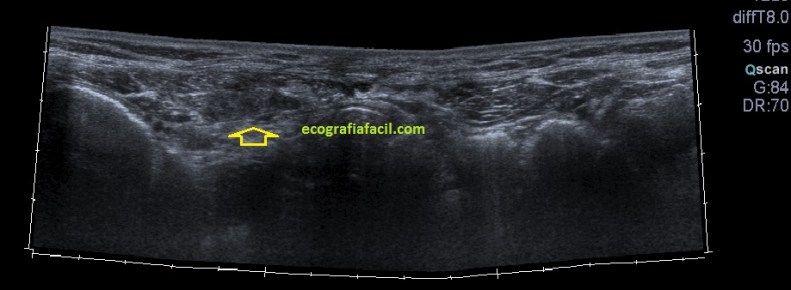

La imagen final demuestra una visión panorámica de los rectos abdominales inferiores demostrando los hallazgos que te he ido explicando durante el post. En este caso me hizo falta utilizar una función del ecógrafo muy útil que es la “función dual”, donde he dividido a pantalla en dos y he podido comparar en una misma imagen tanto a normalidad como la zona patológica, con un considerable aumento de la resolución de la imagen y un aumento en la calidad global de esta tanto en corte transverso como en longitudinal. Esta función dual permite el estudio comparativo con doppler. Muy útil, aunque el almacenamiento masivo de imagen en el pacs hace que esta función haya caído paulatinamente en desuso.